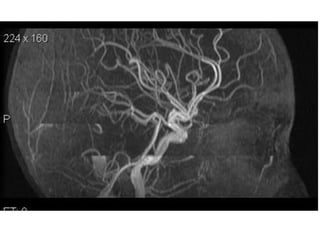

Arteries of the brain (lateral view) - MRA

1. Anterior cerebral artery

2. Anterior communicating artery

3. Basilar artery

4. branches (in insula) of middle cerebral artery

5. Cavernous portion of internal carotid artery

6. Cervical portion of internal carotid artery

7. Genu of middle cerebral artery

8. Intracranial (supraclinoid) internal carotid artery

9. Middle cerebral artery

10. Ophthalmic artery

11. Petrous portion of internal carotid artery

12. Posterior cerebral artery

13. Posterior cerebral artery in ambient cistern

14. posterior cerebral artery in interpeduncular

cistern

15. Posterior communicating artery

16. Posterior inf cerebellar artery.

17. Quadrigeminal portion of posterior cerebral

artery

18. Superior cerebellar artery

19. Vertebral artery